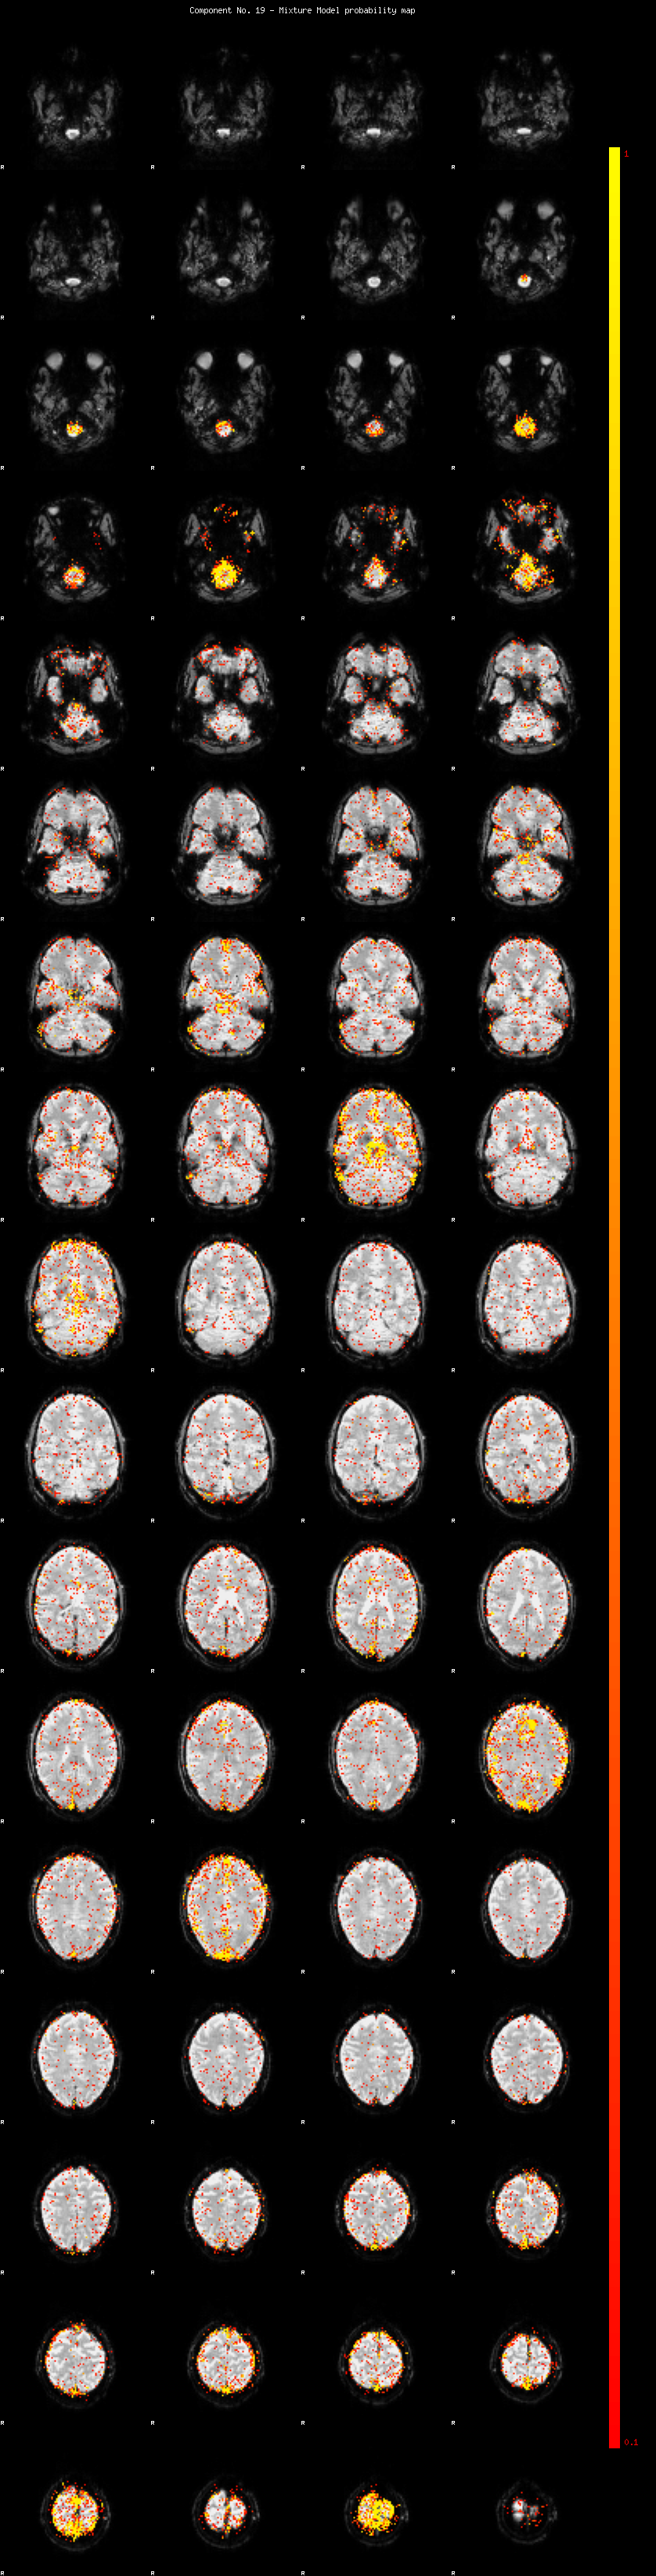

IC_19 Mixture Model fit

Means : -0.000000 3.194658 -2.728017

Vars : 1.000000 4.848854 2.941576

Prop. : 0.938754 0.033165 0.028080